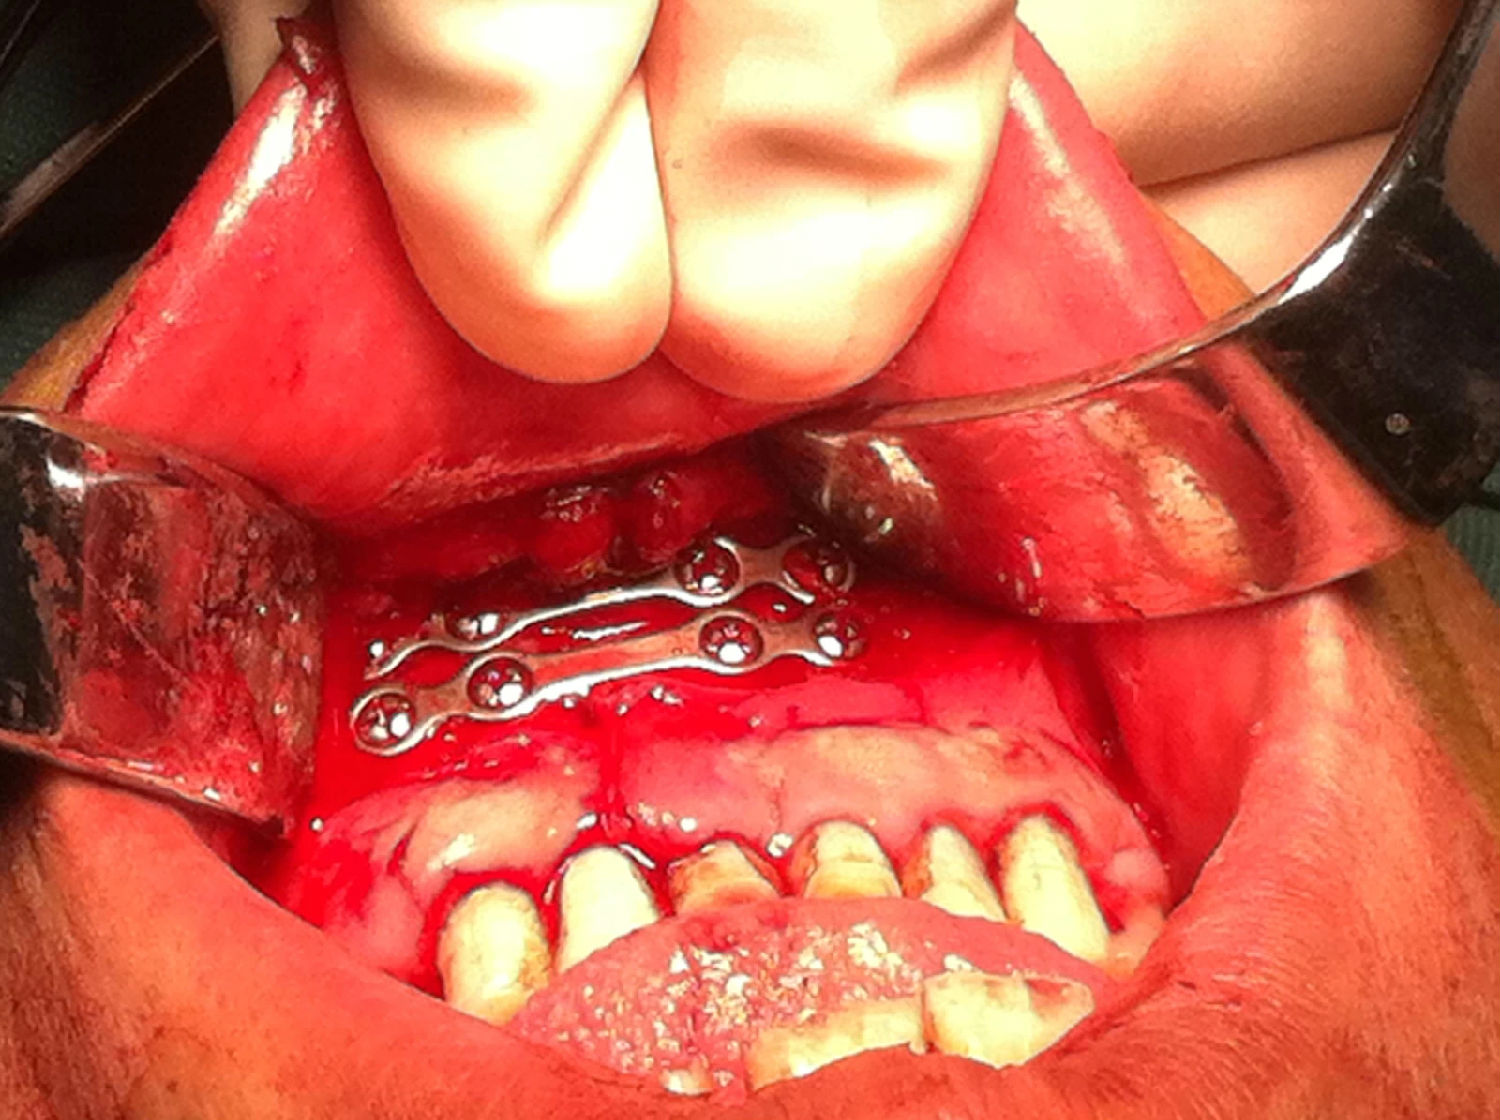

入院后全麻下手術(shù)治療,左側(cè)下頜骨囊腫較大,術(shù)前考慮病理性骨折可能,準(zhǔn)備鈦釘鈦板固定,術(shù)中摘除囊腫后,發(fā)現(xiàn)下頜骨下緣骨量尚可,未給予固定。術(shù)后病理診斷為下頜骨角化囊腫,考慮到患者可能為基底細(xì)胞癌綜合征,術(shù)中切除頸部皮膚痣兩處,術(shù)后病理診斷為:皮膚痣,排除基底細(xì)胞癌綜合征?;颊哂凶髠?cè)第六肋骨分叉肋,綜合以上特征,最終診斷為多發(fā)性頜骨囊腫綜合征。